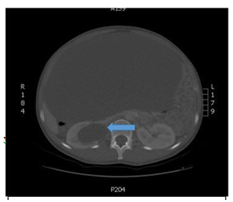

24 year old female patient who attends to overall control, at the time of referred was found asymptomatic in history but I indicated that her mother had died of liver sarcoma no other antecedent family, personal or surgical, referred menarche at 13 years, with regular menstrual cycles without recent changes from cycle frequency or amount of menstrual bleeding, condom use as a method of family planning for 6 years, when no gestational history, clinical examination only increased abdominal girth positive ascetic wave was evident, no changes in abdominal surface vasculature, masses or palpable organ enlargement were evident, no abdominal pain or discoloration of skin or mucosa, thus possible ascites was considered establish and given rise to this initial studies to study origin of ascites were requested. During the next control, no changes compared to previous clinical examination were evident in paraclinical transaminases and bilirubin. the reports in normal parameters, hematology and normal clotting times, quantitative BHCG<0.10mIU/mL (negative) and abdomen total ultrasound showed limited by the large amount of free fluid in the abdominal cavity, with decreased bilateral renal size and dilated right renal pelvis, study no proper evaluation of abdominal organs was achieved by a free liquid, the above clinical suspicion gave gynecopathologists possible neoplasic whereby extension tests were completed including abdominal tomography contrast to study possible neoplastic lesions. For the next control in clinical examinations showed a normal peripheral blood smear, differential protein and globulin normal blood, a 0.90mg/dl for CKD-EPI GFR 88.3mL/min/1.73m2, HIV testing and syphilis serology negative, alpha-fetoprotein 0.9ng/dl (negative), carcinoembryonic antigen 1.32ng/ml (negative), CA 07.16 19.9 IU/ml (negative), CA 125 8.98UI/ml (negative) and the CT abdomen which was evident great mass apparently left adnexal cystic density occupies the whole of the abdominal cavity with mass effect on abdominal organs. Figure 1 & Figure 2 with compressive effect on the right proximal ureter setting moderate hydronephrosis, Figure 3. Therefore requested assessment by the Gynecologic Oncology Service, which program for exploratory laparotomy. Day May 19, 2018 was performed in the patient exploratory laparotomy, where a large cystic mass dependent left annex of about 35cm in major diameter was found. The colour pearlescent compromising left ovary, compression and abdominopelvic displacement organs which tumor resection of the left ovary, omentectomy and appendectomy was performed, samples were sent to pathology for initial study by freezing and subsequent histopathology block. The pathology report indicated: cyst benign ovarian serous papillary cystadenoma consistent, residual ovarian parenchyma with simple epithelial follicular cysts and inclusion in the other samples not suggestive evidence for histopathological changes. Neoplasms, acute or chronic conditions; cytology extracted cyst fluid was negative for malignancy. The patient is discharged after two days without, currently present complications of surgical procedure in outpatient clinical follow by the mass of secondary ovarian origin hydronephrosis.

Figure 1 In sagittal section, a cystic mass is observed that occupies a large part of the abdominal cavity, approximate dimensions of 37x13.8x27cm. In addition, the displacement of intra-abdominal organs.